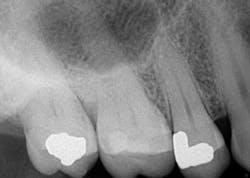

Such is the case for the patient who presented with a chief complaint of biting and occasional slight cold sensitivity on his upper right back molar (No. 2). The patient stated that it hurt to chew and that he wanted to get his tooth fixed as soon as possible. Upon radiographical examination, the periapical for No. 2 was normal. Clinically, the tooth presented with a conservative occlusal amalgam with caries distal to the restoration. In addition, a fracture line on the mesial and distal marginal ridges was noted. Percussion and cold testing were normal and periodontally, the tooth was stable. Bite assessment with the tooth sleuth revealed a positive response on the lingual cusp when biting and releasing. Diagnosis: reversible pulpitis secondary to a crack.

At the crown appointment, the amalgam filling and compromised mesial and distal marginal ridges were removed. The fracture line was indeed detected and noted to extend across the floor in a mesial/distal fashion.Fig. 3